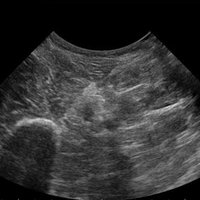

Das Ultraschallsystem MyLab™One zeigt exemplarisch den modernen Bedarf an Diagnosekapazitäten in verschiedenen Anwendungsbereichen: Radiologie, Kardiologie, Phlebologie, Frauenheilkunde, Orthopädie, Regionalanästhesie, Sportmedizin, Interventionell, Rheumatologie, Erste Hilfe, Notfallmedizin, Vaskuläre Reihenuntersuchungen, Allgemeinpraxis.

Kompromisslos für den Point-of-Care: konzipiert für Ihre Umgebung

• Breites Bild mit hoher Qualität